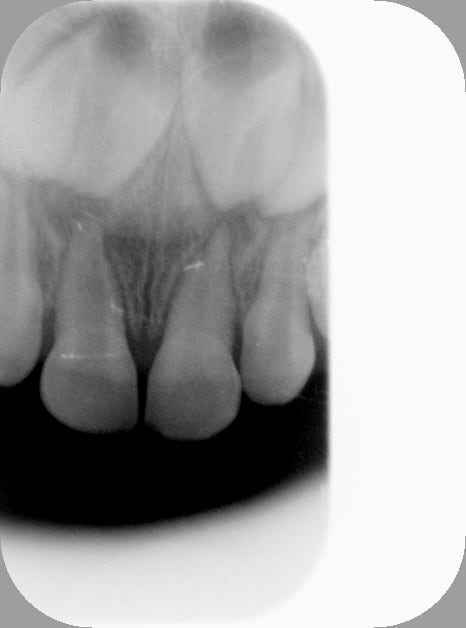

Tiens, je viens de faire ça il y a 5 min, ça me semblait à propos.

Petite vue en mars 2013, 51 dyschromiée suite à chute, 3 ans et demi à l'époque, je la sentais un peu jeune pour tenter le coup.

Pas d'image apicale, pas de fistule.

Revue ce jour, avec les frangines: apparition d'une fistule, décision de l'endo, faite en 5 min. Gamine super cool, pas eu besoin d'anesthésie. 4 ans et 11 mois ce jour. Ordonnance d'antibio en cas de réveil infectieux dans les jours à venir.

Obturation Sealite+IRM dans la chambre, ça tiendra jusqu'à la chute de la dent.